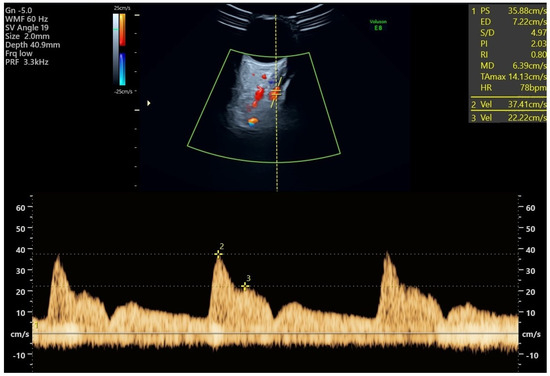

All study participants had Doppler measurements of both ophthalmic arteries taken at their regular visit at 19 + 0 to 22 + 6 weeks of gestation. PE screening utilizes three indices: the ratio of the second peak systolic velocity to the first (PSV2/PSV1), the first peak systolic velocity (PSV1), and the second peak systolic velocity (PSV2) [17,18,19]. The expectant individual ought to be positioned supine and allowed to undergo a five-minute period of rest prior to undergoing the measurements. It is recommended to have the eyes closed. Following the application of lubricant, a transversely oriented linear transducer operating at 7.5 MHz is positioned on the eyelid. The ophthalmic artery ought to be readily distinguishable via color Doppler. The vessel is situated in a medial and superior position along the optic nerve, manifesting as a hypoechogenic band on the scan [20]. The test needs to be carried out using a pulsed-wave Doppler instrument with a 2 mm sample gate, a 125 kHz pulse repetition frequency, a 50 Hz high-pass filter, and an angle of insonation less than 20 degrees. Three to four vibrations ought to be recorded (Figure 1). To prevent untoward effects, the duration of the examination for each eye should not exceed a few seconds. To optimize performance, it is recommended to acquire two measurements for each eye [21,22,23,24]. The operator had previously passed practical assessment in obtaining and analyzing Doppler measurements of the ophthalmic artery and conducted measurements for more than 12 months before enrolling patients in the study.

Figure 1.

Ophthalmic artery Doppler study: an ultrasound image shows the ophthalmic artery’s color flow. The ocular artery flow velocity waveform, which shows the first and second systolic velocities, is displayed at the bottom and was obtained using pulsed-wave Doppler imaging.